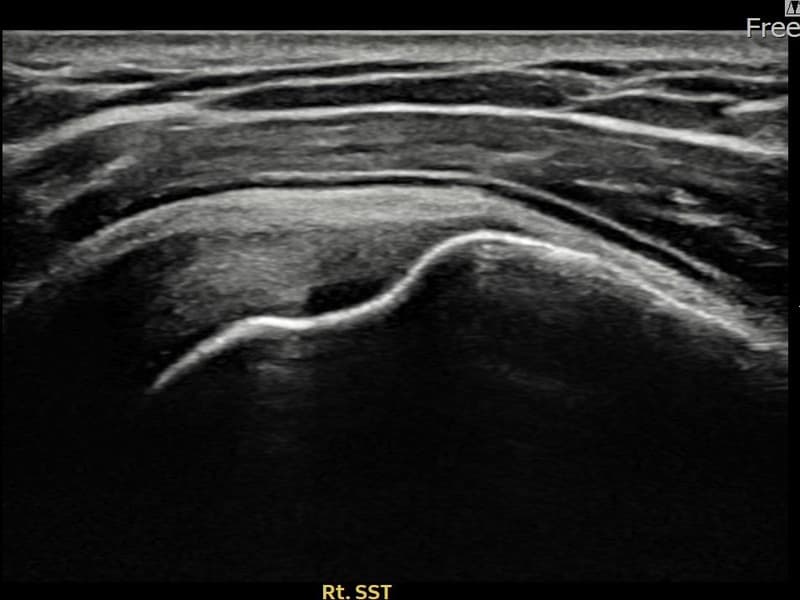

术后

术前超声确认右侧 冈上肌腱 附着部部分撕裂,右侧冈上肌腱回声不连续伴肌腱缺损(10mm × 4mm (肌腱厚度约42%缺损))。术后超声显示撕裂部位充满再生组织,肌腱连续性恢复,回声模式正常化。